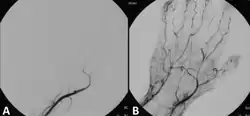

Medication

Those unsuitable for surgery may receive thrombolytics. In the past, streptokinase was the main thrombolytic chemical. More recently, drugs such as tissue plasminogen activator, urokinase, and anisterplase have been used in its place. Mechanical methods of injecting the thrombolytic compounds have improved with the introduction of pulsed spray catheters—which allow for a greater opportunity for patients to avoid surgery.[13][16] Pharmacological thrombolysis requires a catheter to be inserted into the affected area, attached to the catheter is often a wire with holes to allow for a wider dispersal area of the thrombolytic agent. These agents lyse the ischemia-causing thrombus quickly and effectively.[17] However, the efficacy of thrombolytic treatment is limited by hemorrhagic complications. Plasma fibrinogen level has been proposed as a predictor of these hemorrhagic complications. However, based on a systematic review of the available literature until January 2016, the predictive value of plasma is unproven.[18]

Mechanical thrombolysis

Another type of thrombolysis disrupts the clot mechanically using either saline jets or, more recently, ultrasound waves. Saline jets dislodge the clot using the Bernoulli effect. Ultrasound waves, emitted at low frequency, create a physical fragmentation of the thrombus.[19]